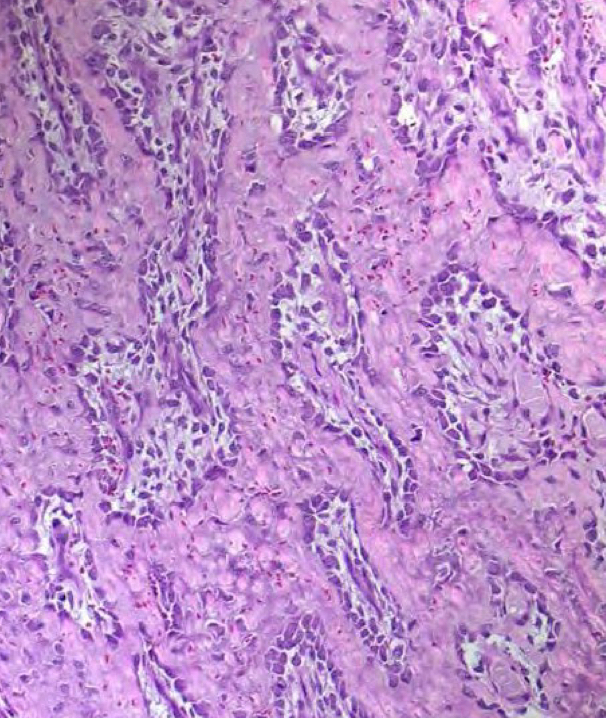

Label this image

A

Osteoblasts are rounded, form a single row of cells along trabeculae.

Osteocytes are thinner and located within lacunae embedded in bone.

Osteoclasts are multinucleated cells located along trabeculae and will resorb bone under stimulation of cytokines secreted by osteoblasts or inflammatory cells